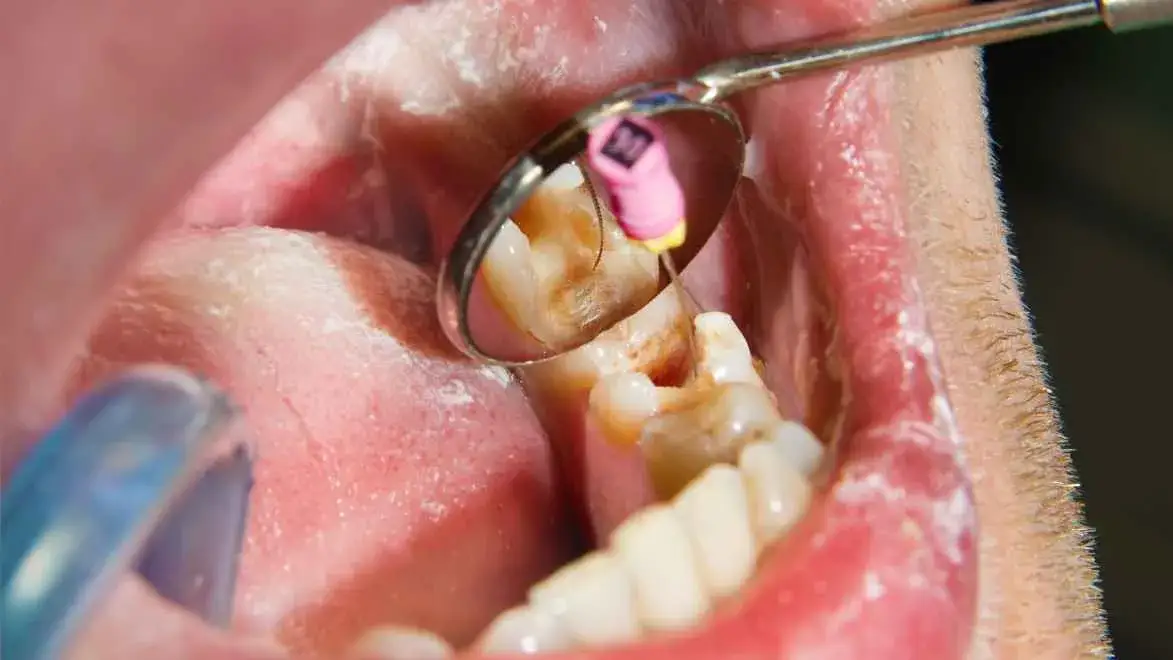

Jak głęboko sięga problem? Ocena ubytku próchnicowego na rentgenie

Zdjęcie RTG jest również niezastąpione do oceny głębokości ubytku próchnicowego. Pozwala mi precyzyjnie określić, czy próchnica dotarła już do komory zęba, gdzie znajduje się miazga. Często na powierzchni zęba ubytek może wydawać się niewielki, ale na rentgenie okazuje się, że rozprzestrzenił się on znacznie głębiej, zagrażając żywotności miazgi.

Głęboka próchnica jako główny winowajca

Bez wątpienia, głęboka próchnica jest najczęstszą przyczyną problemów z miazgą. Kiedy bakterie próchnicowe przenikają przez szkliwo i zębinę, docierają do miazgi, wywołując jej stan zapalny. Jeśli próchnica nie zostanie wyleczona na wczesnym etapie, infekcja postępuje, prowadząc do nieodwracalnego zapalenia, a w konsekwencji do martwicy miazgi.

- Głęboka próchnica lub widoczne pęknięcie zęba, które mogło dotrzeć do miazgi.